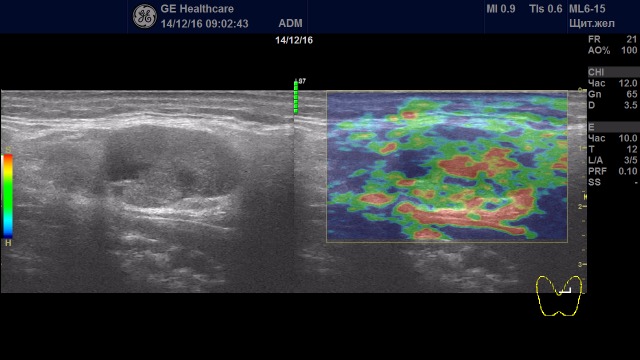

Образования с удовлетворительной эластичностью (тип I-III)

Образование с удовлетворительной эластичностью